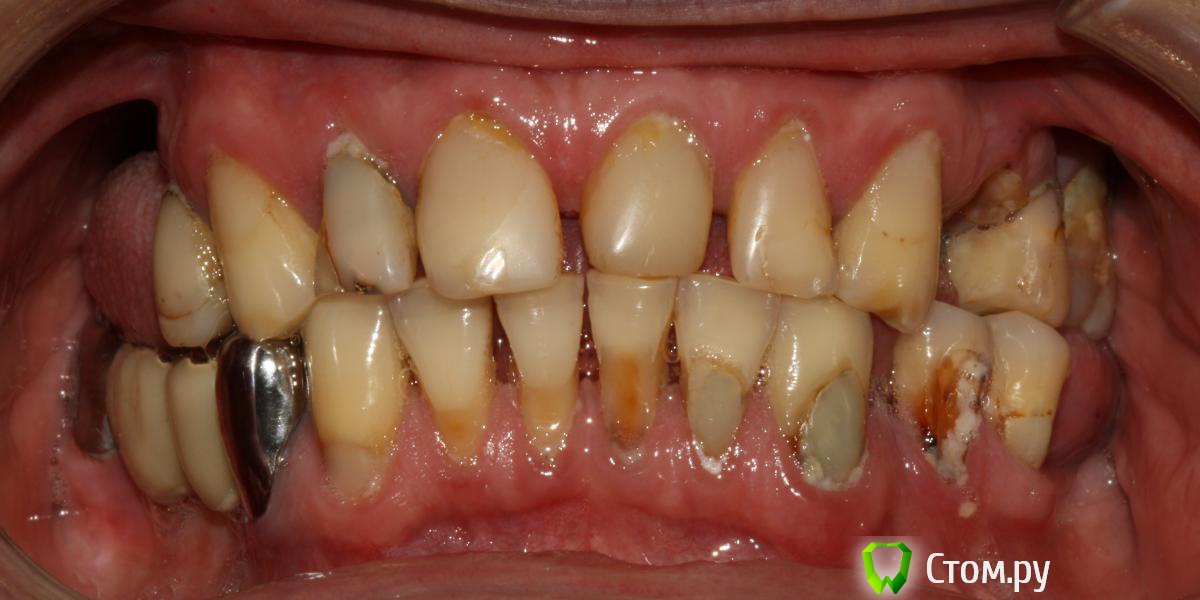

Привет всем! уважаемые Гуру помогите с планированием реабилитации данного пациента. Основная жалоба, не хочет носить съемный протез (пришел из другой клиники, где рекомендовали только съемное протезирование).

Провели обследование. Ортопед планирует оставить вверху 6 фронтальных зубов (возможно резцы пойдут на удаление), внизу только клыки. Далее последует удаление несостоятельных зубов + иммедиат протезы, продолжение реабилитации.

п.с. ДА, С ГИГИЕНОЙ ПОКА ЗАСАДА!!!)

Почему этому пациенту отказали в имплантации, предложив съемное протезирование?

В клинике, в которую он обращался, реабилитацию с помощью имплантатов проводят лет 8, может больше.